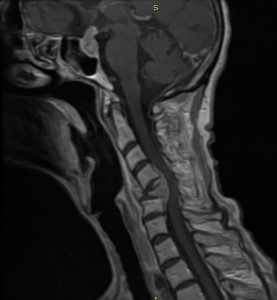

Πρόσθια – Οπίσθια (360ο) Σπονδυλοδεσία Αυχενικής Μοίρας Σπονδυλικής Στήλης